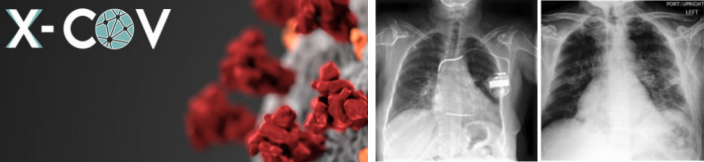

項(xiàng)目名稱:AI技術(shù)在肺部醫(yī)學(xué)診斷的應(yīng)用(西班牙 X-COV公司)

西班牙馬德里一家初創(chuàng)企業(yè),由醫(yī)學(xué)院的多名教授和學(xué)生聯(lián) 合成立,其開發(fā)出一款用于協(xié)助醫(yī)生分析胸腔 X光片的人工智能 工具,這使得醫(yī)生對(duì) X光片的分析結(jié)論更客觀準(zhǔn)確,通過深度學(xué) 習(xí),其分析準(zhǔn)確率達(dá)到 90%以上,假陰性為零。這款工具可通過 線上方式協(xié)助醫(yī)生,使得因疫情而暴增的 X光片被快速且準(zhǔn)確地 分析。同時(shí),該企業(yè)在開發(fā)新的版本,以融入醫(yī)院現(xiàn)有的醫(yī)學(xué)影 像存檔及傳輸系統(tǒng)。該企業(yè)的這款工具在今年的世界級(jí)黑客馬拉 松競(jìng)賽中獲得了眾多醫(yī)學(xué)專家和公司的關(guān)注。